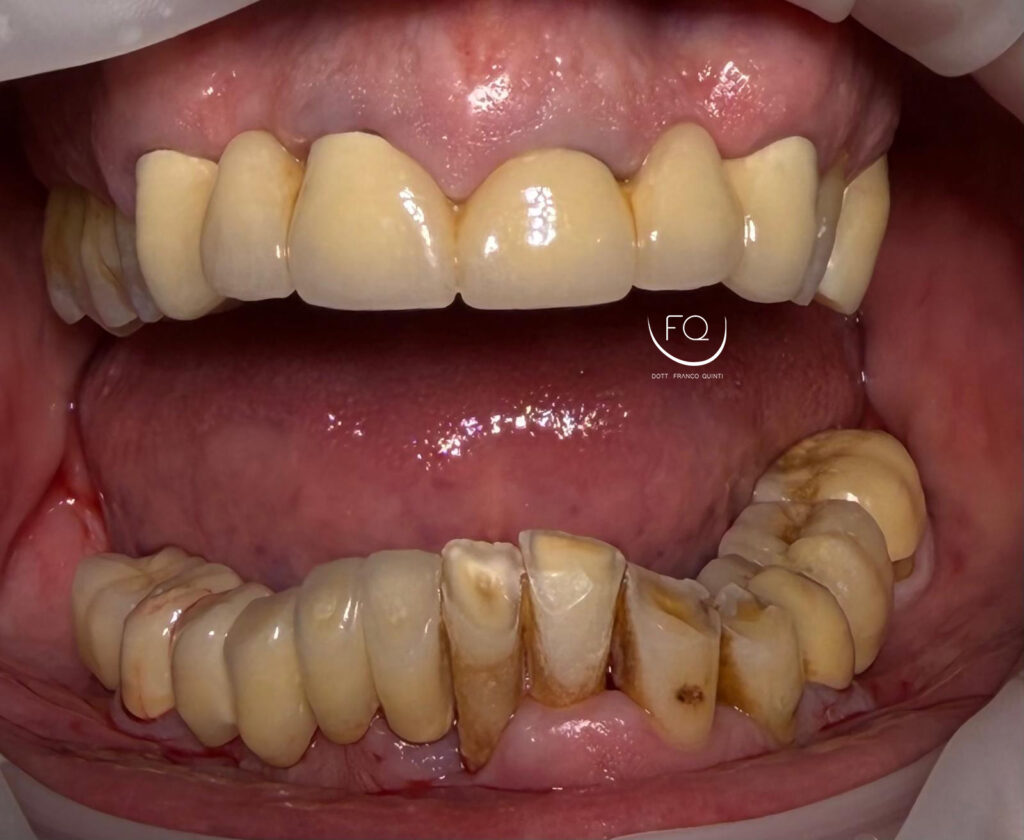

Dall’immagine iniziale è possibile apprezzare l’estrusione del gruppo incisivo inferiore il quale è stato corretta con la protesi provvisoria a carico immediato stampata in 3D.